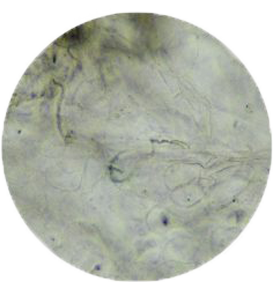

ㆍ黴菌檢查(KOH)

用來檢查皮癬菌、念珠菌、皮屑芽苞

菌的檢查,可用來診斷足癬、體癬、

頭癬、手癬、汗斑、念珠菌感染等。